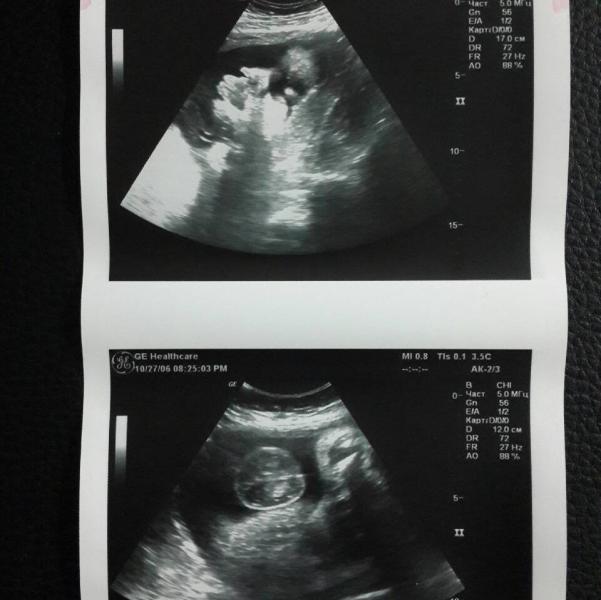

Наше личико и яички....😊😊😊